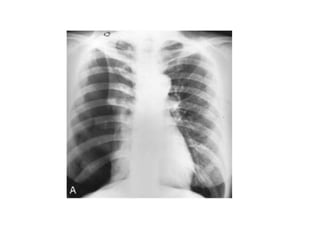

RADIOGRAPHICDIAGNOSIS

1- CXR

The standard procedure in making the diagnosis.

 It should be upright and preferably in the posteroanterior

projection. It is possible to miss a pneumothorax in a

semisupine portable anteroposterior view. If the patient

cannot be upright, a lateral decubitus view with the suspect

side positioned up may be helpful.

 A giant bulla can mimic a pneumothorax. Subtle lines demarcate

a bulla, which tends to be surrounded by thickened visceral pleura.

In addition, a pleural line can frequently be seen with lung

markings visible beyond the suspected bulla (double wall sign)

• British Thoracic Society guidelines for the

management of spontaneous pneumothorax,

recommend defining pneumothoraces as:

I. small defined as small rim of air around the

lung

II. moderate as lung collapsed halfway towards

the heart border

III. complete as airless lung, separate from the

diaphragm.